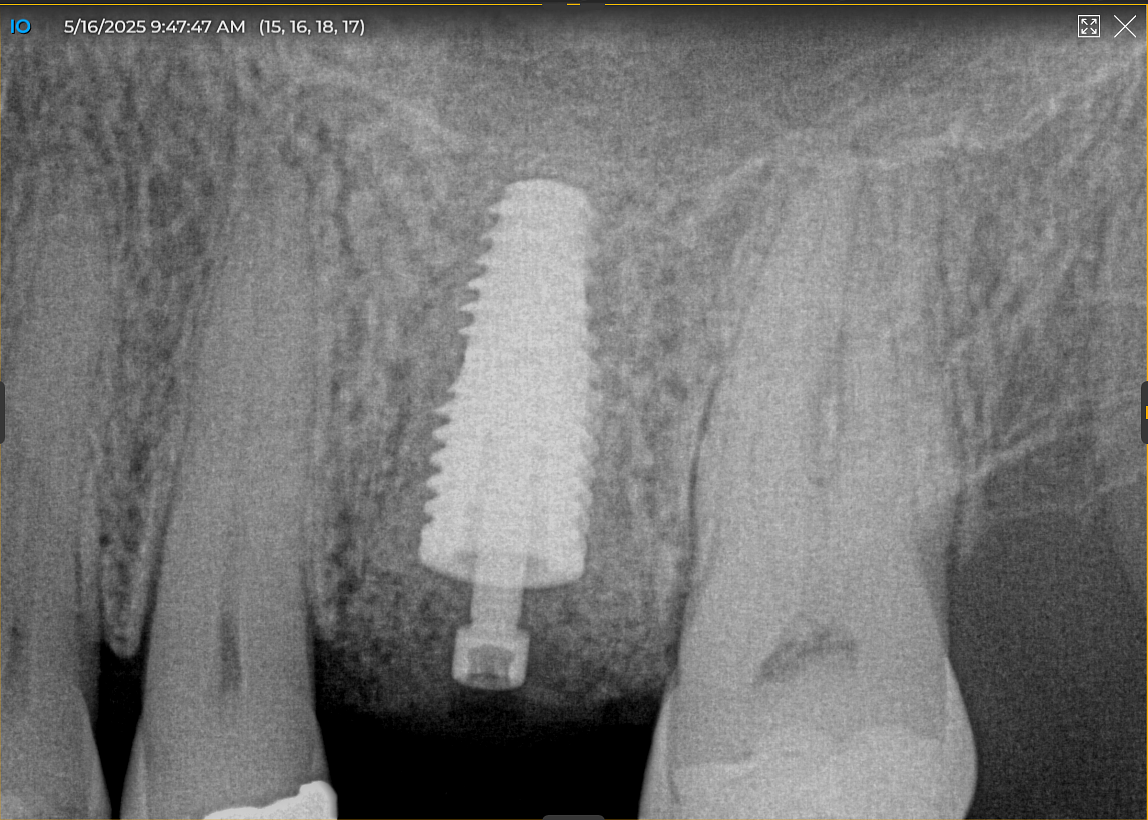

First, I layered a 20 × 30 collagen membrane and draped it from the buccal across to the palatal walls. Then I placed a 12 x 30 cytoplast PTFE membrane and secured both membranes with sutures. I wanted to leave the cytoplast for six weeks due to the size of the defect and graft, so I used both PTFE and glycolon sutures. The postoperative PA showed excellent bone fill that was dense.

At four months, patient returned and records were made for the implant process. Records showed good bone fill and good bone height, the implant was planned on exocad software and a guide was fabricated.

Today, we placed the implant, scanned for the final restoration, just like teaches us to do, and I placed a Neodent healing abutment.